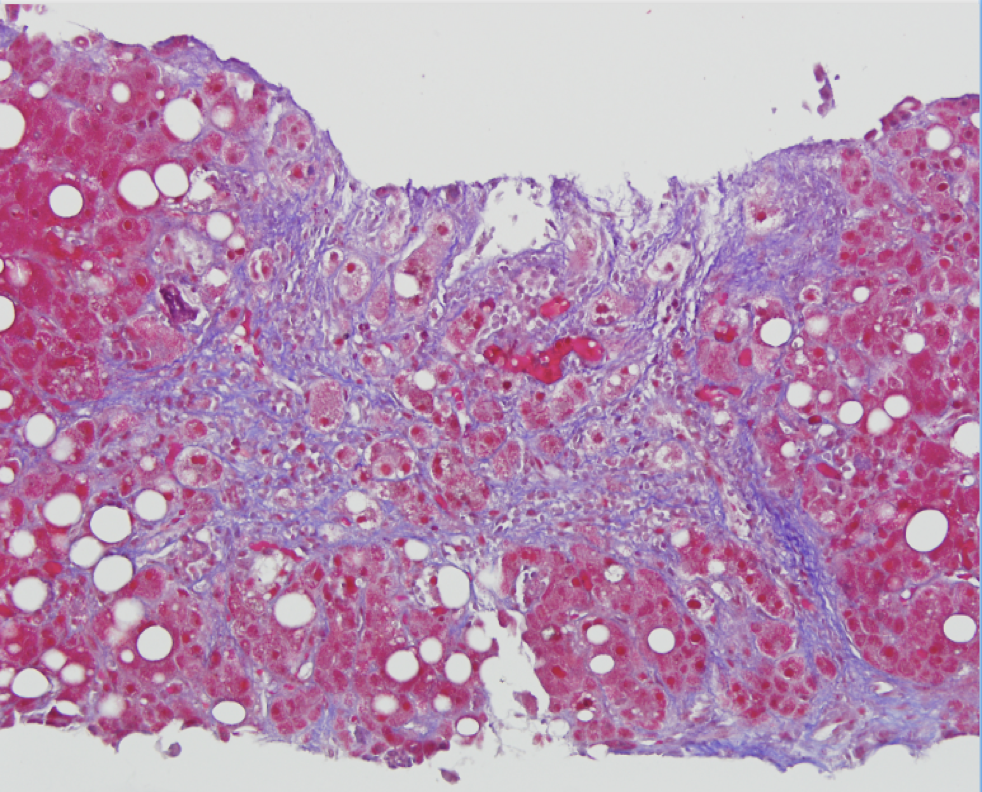

Meanwhile, the patient’s bilirubin continued to rise to 20 mg/dL. Next, a transjugular liver biopsy with pressure measurements was performed with a hepatic venous pressure gradient of 10 mmHg, confirming portal hypertension. Histology showed steatosis, mild portal fibrosis, and Mallory body formation with neutrophilic infiltrates, consistent with a diagnosis of alcoholic hepatitis. He was started on prednisolone and completed a 28-day course of steroids with complete resolution of fevers, ascites, and biochemical abnormalities.